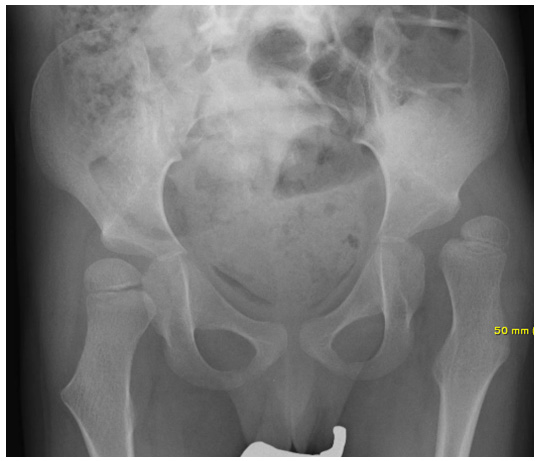

Figure 2: Boy GMFCS 5, 7 years old with complete dislocation of the left hip left and subluxation on the right.

figure 2